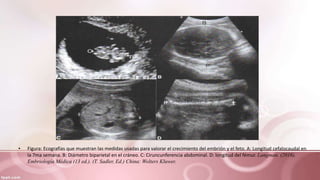

• De la quinta a la decima semana de gestación, la edad y el

crecimiento del feto se determinan mediante la longitud

cefalocaudal

Después se usa:

• Diametro biparietal (DBP)

• Longitud del Femur

• Circunferencia abdominal

• Figura: Ecografías que muestran las medidas usadas para valorar el crecimiento del embrión y el feto. A: Longitud cefalocaudal en

la 7ma semana. B: Diámetro biparietal en el cráneo. C: Ciruncunferencia abdominal. D: longitud del fémur. Langman. (2016).

Embriología Médica (13 ed.). (T. Sadler, Ed.) China: Wolters Kluwer.